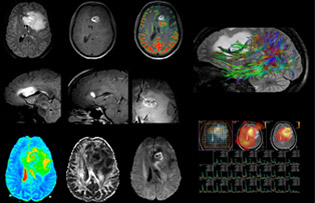

“In France, every stroke is usually imaged with MRI, not CT, even for emergency treatment.” “In France, stroke is usually imaged with MRI, not CT, even for emergency treatment. This is because MRI helps us directly visualize ischemia in the acute phase, but can also help rule out differentials such as MS and hematoma. In addition, we can assess the intracranial and extracranial vessels during the same examination,” says Dr. Savatovsky.

The first challenge in MRI of stroke is speed. The patient typically arrives from an ambulance in the MRI preparation room and the installation is done on a separate dock outside the scanner room. “The venous access is placed during the neurological examination. If the delay from the first symptoms allows the patient to receive thrombolysis we do a very fast examination that typically lasts about 11 minutes including the pre-scans. In the case of transient ischemic stroke we usually add ASL perfusion because in some symptoms with negative diffusion, ASL sometimes indicates a vascular origin.”

“Ingenia provides great flexibility in the parameters setting. We can tune a sequence the way we want,” says Dr. Savatovsky. “For example, in a stroke exam we use a FLAIR sequence of about two minutes instead of the four-minute FLAIR we use for MS. The diffusion is 30 seconds, the T2*-weighted scan is 30 seconds, the angiography scan time is less than one minute. Ingenia is a great scanner in that situation; even with these fast sequences we can achieve good images with good SNR. When the first sequence tells us that it’s not an ischemic stroke but a hemorrhagic stroke, we may switch to a time-resolved angiography to look for vascular malformations and venous thrombosis.

“Every center is different, but for me the ideal protocol for stroke includes diffusion weighted imaging, FLAIR, and fast susceptibility imaging,” says Dr. Savatovsky. “Our fast susceptibility weighted imaging takes 50 seconds, so it’s as fast as T2*-weighted imaging. It visualizes hemorrhage but also the clots. We also do 3D MR angiography that provides information on cervical and brain vessels. If the patient does not need immediate treatment, or if additional information is needed to decide on treatment, we might also add perfusion imaging and post-contrast T1-weighted imaging.”